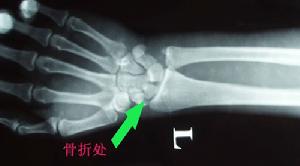

2.X線攝正側斜位片。有時早期骨折線顯示不清可在兩周后再攝片以便確診。

傷後局部腫脹,疼痛,腕關節活動受限並疼痛加重。鼻咽窩處及舟骨結節處有壓痛。第2、3掌骨頭縱向叩擊痛。有時輕微骨折症狀不明顯,與腕扭傷症狀相似,易誤診忽略,腕關節正位、側位、斜位(舟狀位)三種方位X片可確診骨折部位及方向。若骨折不清楚,臨床症狀懷疑骨折時,應暫按骨折處理,待二周后,複查X片。由於骨折處骨質吸收,骨折線能明顯認出。

傷後腕部橈側腫脹疼痛,腕關節活動時疼痛加劇並受限。鼻咽窩及舟骨結節處有明顯壓痛。腕關節橈偏,沿Ⅰ、Ⅱ掌骨長軸叩擊或擠壓時均引起骨折處疼痛。X線片需攝腕關節正、側位及舟骨位三個方向,多能顯示骨折線。有時沒有移位的骨折,早期X線片為陰性。對可疑病例,應在兩周后再照片複查,因傷後骨折處骨質吸收,骨折線增寬而顯出。陳舊性骨折,可見骨折線明顯增寬,骨折端硬化或囊性變,這是骨不連線的表現,若近段骨塊密度增加、變形等則為缺血性壞死。

骨折線多在舟骨腰部,骨折塊雖無較大之移位,但兩折端間往往有間隙。

舟骨骨折按骨折發生的部位分為舟骨中段骨折、近段骨折和結節部骨折。舟骨骨折的骨折線如錯位不明顯時,須留意下列可提示診斷的徵象:①舟骨結節的骨皮質斷裂;②舟骨結節部或頭舟關節間隙內的小游離骨折片;③舟骨一側或雙側關節面骨皮質出現中斷或有垂直於關節面的細小裂隙、皺摺、台階樣改變。